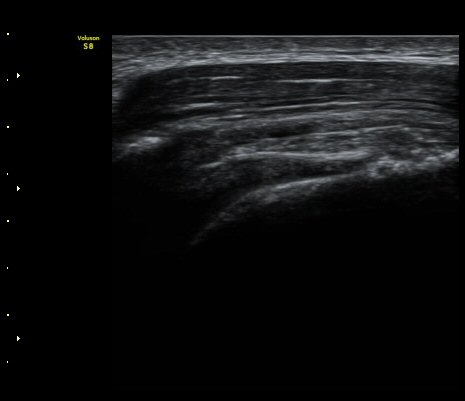

ÀϺΠ±Ø»ó°Ç Á¾´Ü¸é°Ë»ç¿¡¼­ ±Ø»ó°ÇÀÇ ÀüÃþÆÄ¿­°ú ±Ø»ó°Ç¸¦ ¿¬°áÇÑ ºÀÇջ簡 ±¸ºÒ±¸ºÒ(tortous)ÇϰÔ

°üÂûµÇ¾î ºÀÇÕ»ç ÆÄ¿­À» ½Ã»çÇÑ´Ù(»çÁø 5, 6).